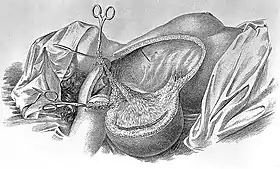

| An illustration of breast cancer | |